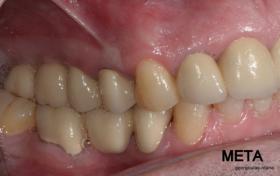

ΠΡΟΣΘΕΤΙΚΗ ΑΠΟΚΑΤΑΣΤΑΣΗ ΣΤΗΝ ΑΝΩ Κ ΚΑΤΩ ΓΝΑΘΟ ΚΑΙ ΤΟΠΟΘΕΤΗΣΗ ΕΜΦΥΤΕΥΜΑΤΩΝ ΜΕ ΚΛΕΙΣΤΗ ΑΝΥΨΩΣΗ ΙΓΜΟΡΕΙΟΥ

Ο ασθενής  προσήλθε στο ιατρείο μας θέλοντας να βελτιώσει την εμφάνιση των πρόσθιων δοντιών του και να αποκαταστήσει την υγεία κ την λειτουργία όλου του στόματος. Πραγματοποιήθηκε περιοδοντική θεραπεία κ ενδοδοντικές θεραπείες (απονευρώσεις) όπου κρίθηκε απαραίτητο και στη συνέχεια τοποθετήθηκαν 3 εμφυτεύματα, 2 δεξιά στις θέσεις του πρώτου κ δεύτερου γομφίου κ 1 αριστερά στη θέση του πρώτου προγομφίου. Κατά την  τοποθέτηση των 2 εμφυτευμάτων της δεξιάς πλευράς, πραγματοποιήθηκε κλειστή ανύψωση ιγμορείου με το σύστημα Piezotome-Intralift , τεχνική που εξασφαλίζει τη μικρότερη δυνατή επέμβαση κ τη μικρότερη μετεγχειρητική ταλαιπωρία (minimally invasive), καθώς κ αυξητικους παράγοντες PRF. Σε όλη τη διάρκεια της θεραπείας  ο ασθενής ήταν καλυμμένος τόσο αισθητικά όσο και λειτουργικά με προσωρινές μεταβατικές αποκαταστάσεις. 4 μήνες μετά την  τοποθέτηση των εμφυτευμάτων κ την οστεοενσωμάτωσή τους, ακολούθησε η τοποθέτηση των μόνιμων αποκαταστάσεων.